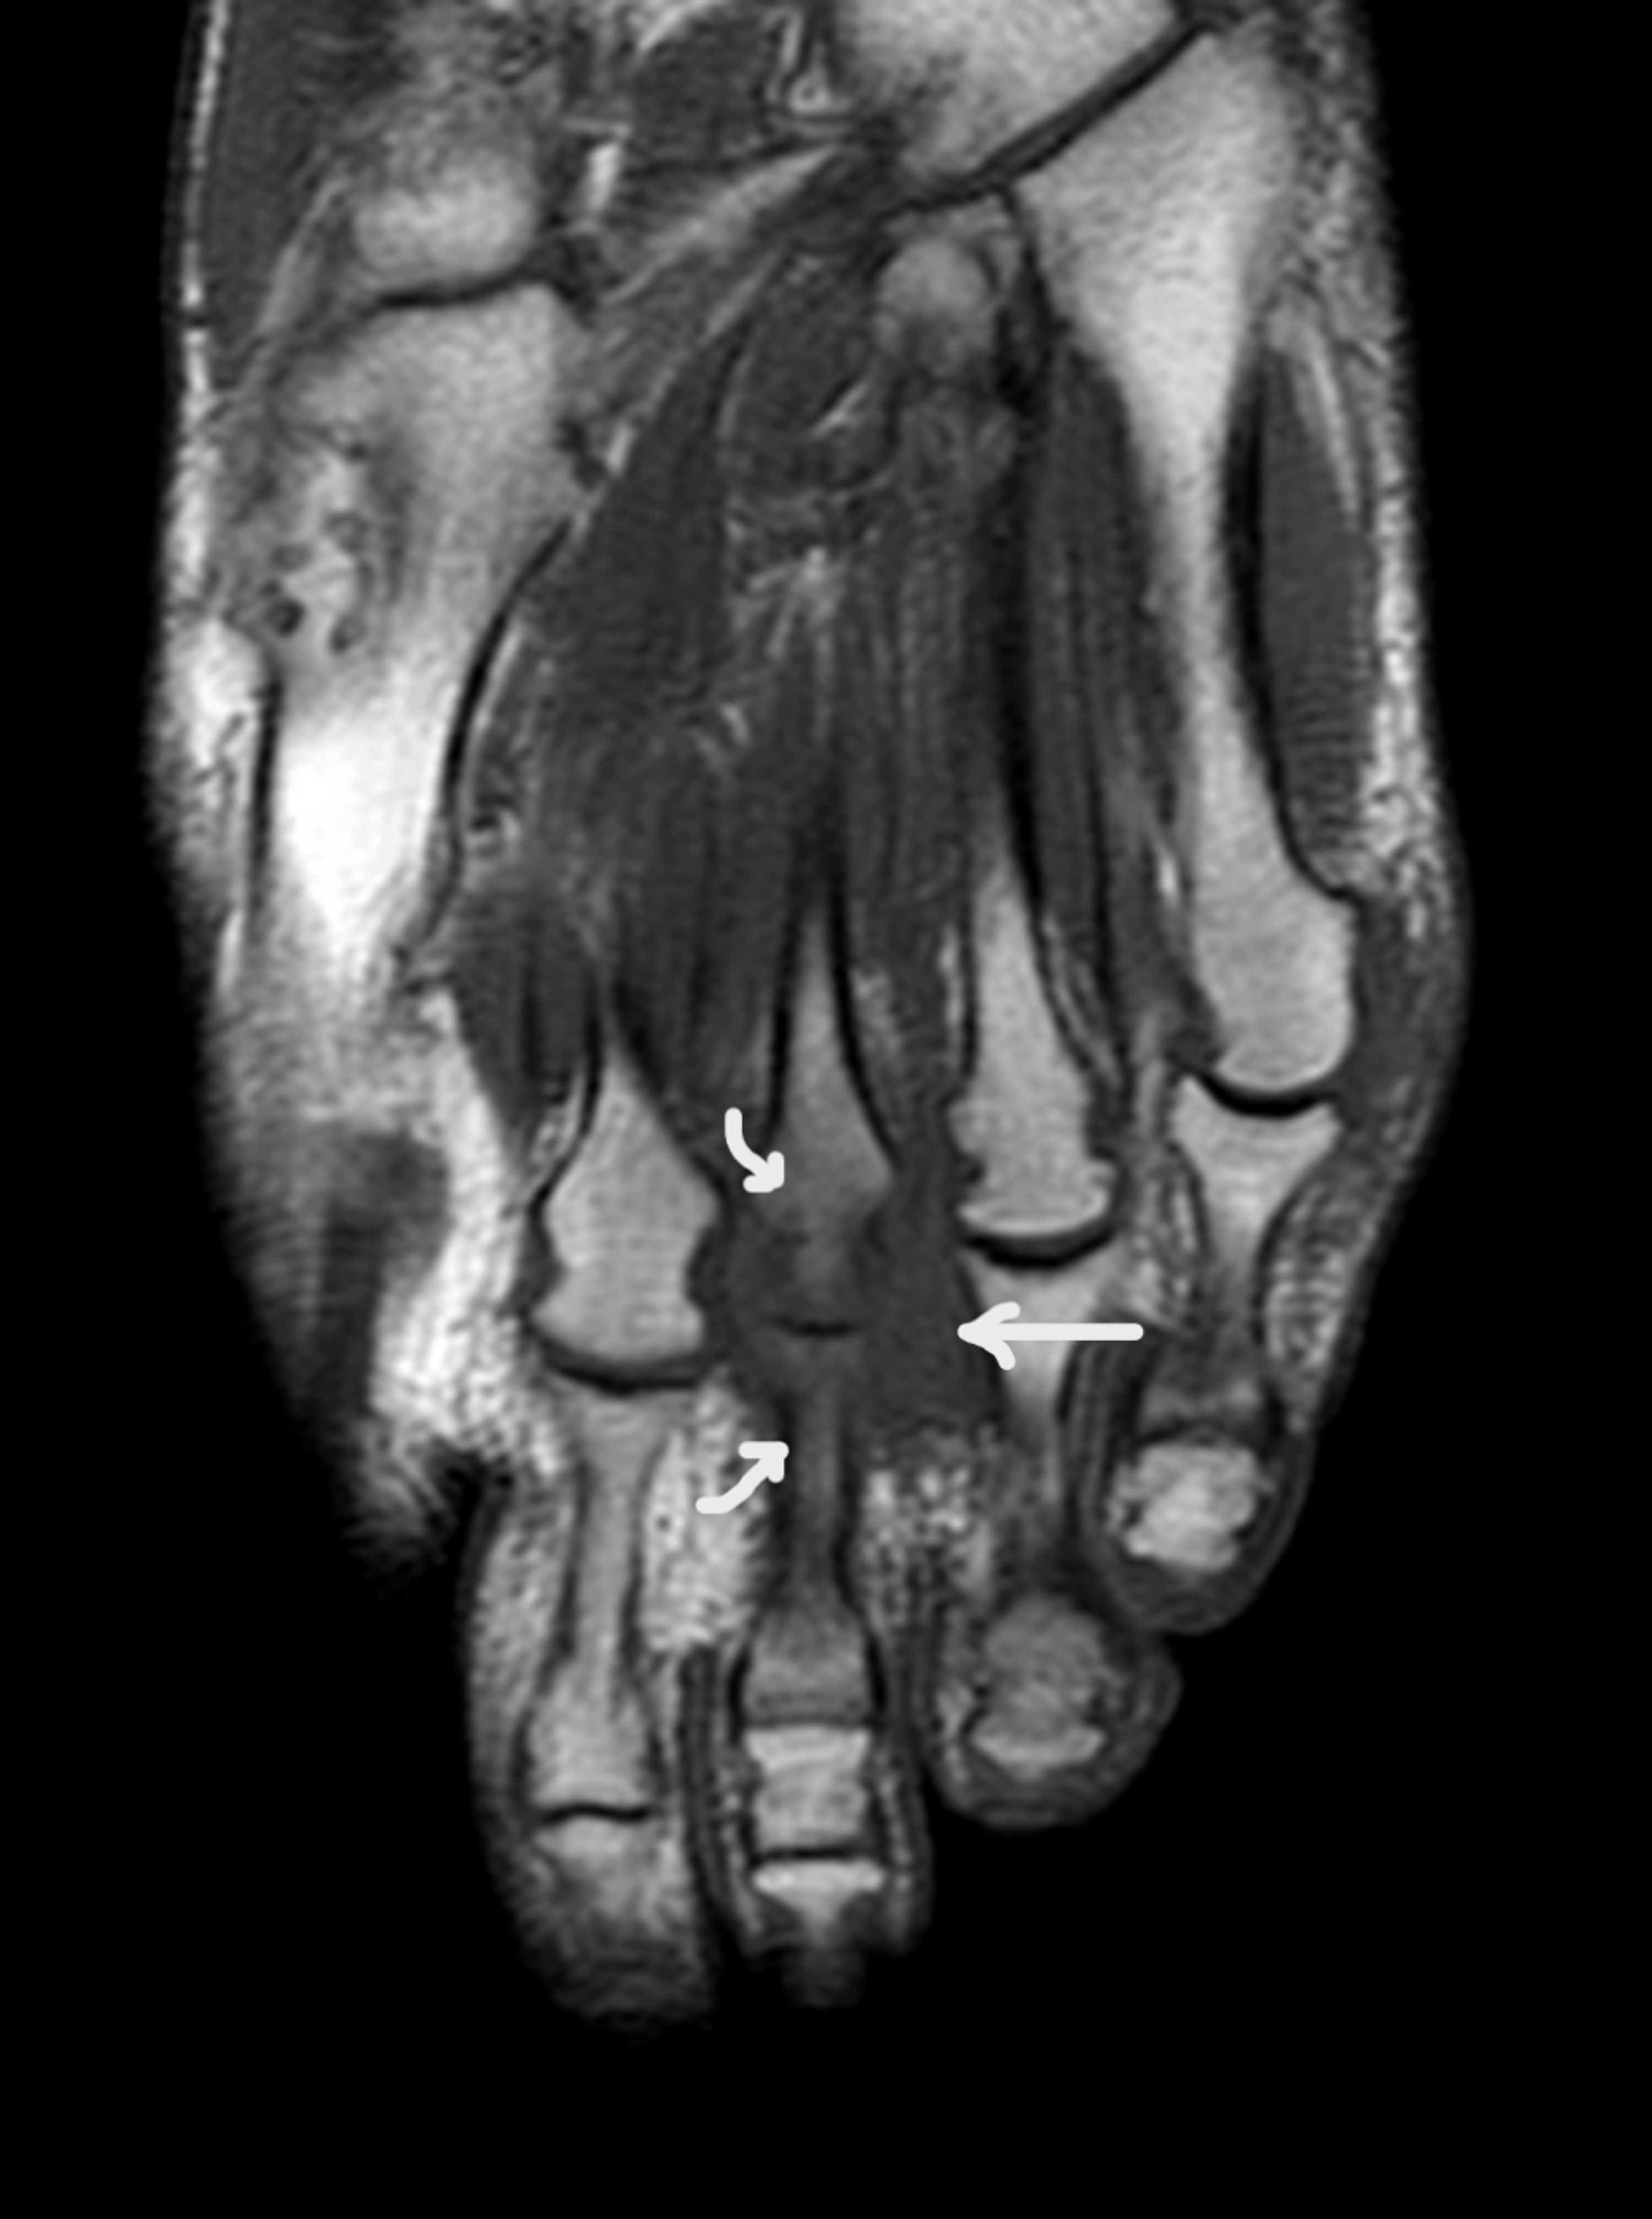

1st Metatarsophalangeal (MTP) joint osteoarthritis ( Big toe arthritis) Metatarsal Arthritis Icd 10 first metatarsophalangeal (mtp) joint osteoarthritis (oa) is a common and painful problem that causes significant disability. This pain usually results from. m77.42 is a billable diagnosis code used to specify a medical diagnosis of metatarsalgia, left foot. hallux rigidus is a common foot condition characterized by pain and loss of motion of the 1st mtp joint in. Metatarsal Arthritis Icd 10.

Hypermobility of the first metatarsal bone in patients with Rheumatoid Metatarsal Arthritis Icd 10 first metatarsophalangeal (mtp) joint osteoarthritis (oa) is a common and painful problem that causes significant disability. what is first toe (metatarsophalangeal) arthritis? This pain usually results from. m77.42 is a billable diagnosis code used to specify a medical diagnosis of metatarsalgia, left foot. hallux rigidus is a common foot condition characterized by pain and loss of. Metatarsal Arthritis Icd 10.